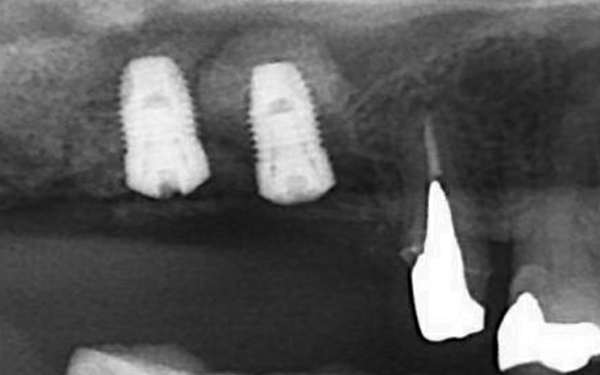

完成時X光片可看見新生骨頭